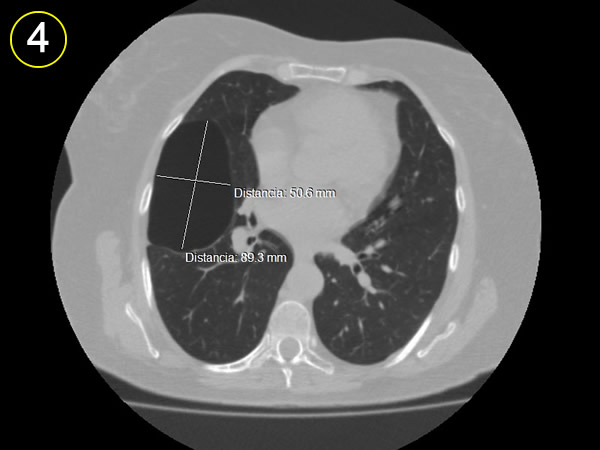

La tomografía

computarizada del tórax

y su adecuada interpretación es de gran ayuda diagnóstica

en las patologias del tórax.